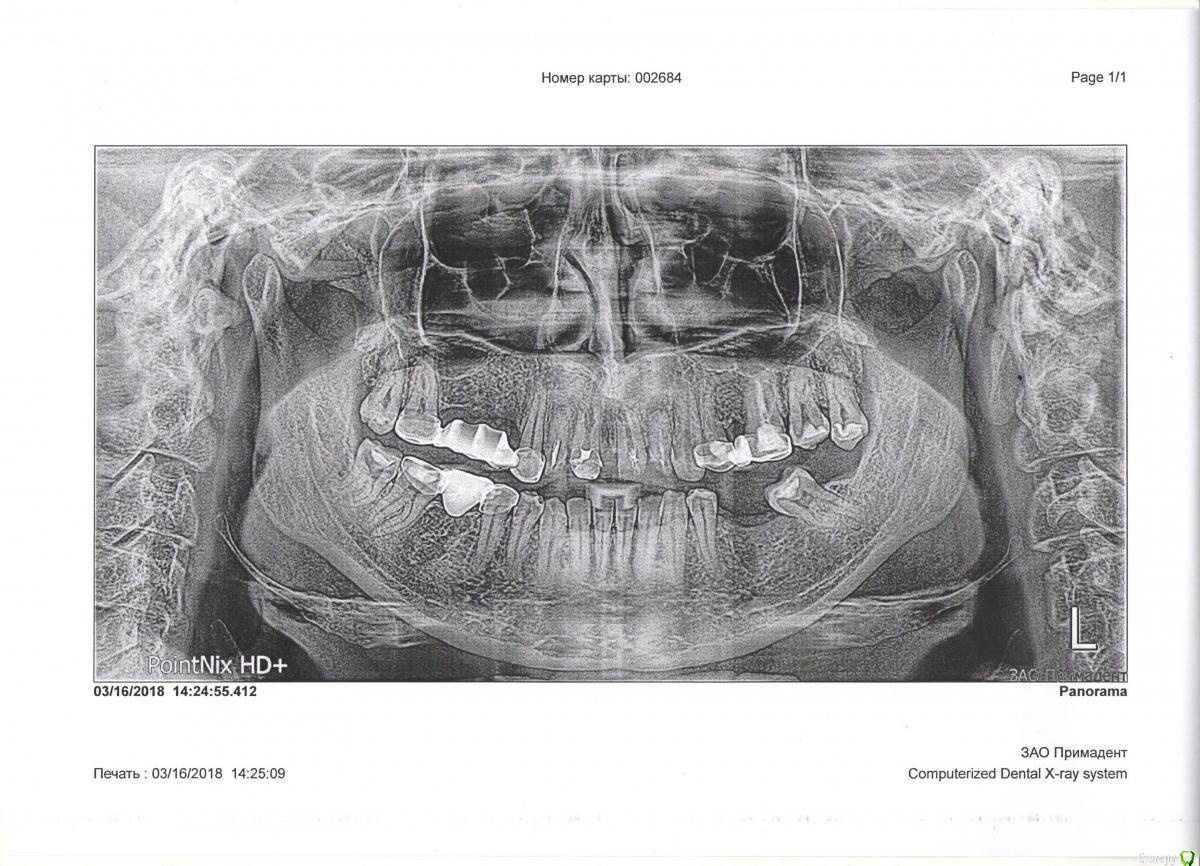

Natalyk Опубликовано 26 марта, 2018 Поделиться Опубликовано 26 марта, 2018 добрый день,помогите в решении,не могу принять морально и физич. имплантацию,пол года до имплантов быть без зубов обещают после удаления верхних 1,2,потом еще пол года приживаться,т.е ,съемный протез.Понимаю,что не лучший мой выбор ,подскажите какой ставить металлокерам. мост ,при удалении 12 по 22?все зубы нужно депульпировать под метал/кер,обтачивать по максимуму?мост?1. 17 по 262. 2 моста 17 по 23 и 24 по 26какой вариант выбрать? Ссылка на комментарий

red_butler Опубликовано 27 марта, 2018 Поделиться Опубликовано 27 марта, 2018 С учетом большой протяженности дефекта, а так же отсутствия трех зубов справа, мостовидное протезирование следует исключить. Ссылка на комментарий

red_butler Опубликовано 27 марта, 2018 Поделиться Опубликовано 27 марта, 2018 спасибо,к сожалению ответ не обрадовал!какие варианты есть?На верхней челюсти имплантация или съемный протез, на нижней имплантанты или мосты Ссылка на комментарий